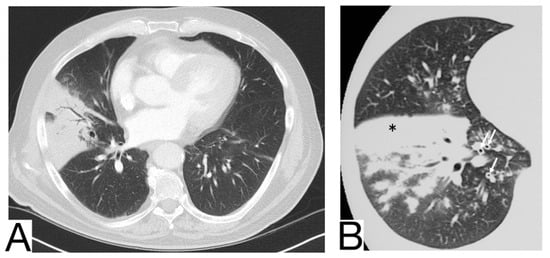

Viral pneumonia is defined as a diverse entity, and it is mainly the current epidemic context that suggests the origin of COVID-19. The treatment proved to be similar at present []. Radiological characteristics in differential diagnosis: preferential central-parenchymal involvement (Influenza type A, Adenovirus, Hantavirus) (Figure 6A); additional findings, such as centrolobular nodules and bronchial wall thickening (RSV, MERS, Influenza type A); coexisting pulmonary edema (Hantavirus); pleural effusions (RSV, MERS); hilomediastinal lymphadenomegaly (Influenzae type A) [,,].

Figure 6. (A). Multifocal areas of poorly defined focal consolidation in a patient positive for influenza A (H1N1) (B). Bilateral ground-glass opacities and dense airspace consolidations in a patient with Pneumocystis jirovecii pneumonia (C). Halo sign in a patient with aspergillosis. Note. Adapted from Elmokadem et al. (2021) [] (A), Sullivan et al. [] (2020) (B), and Dr. Laughlin Dawes (C).

10.3. Pneumocystis Pneumonia

Pneumocystis pneumonia is an opportunistic fungal infection that mainly affects immunodeficient patients affected by AIDS or undergoing immunosuppressive therapy (Figure 6B) []. History and laboratory tests are helpful but often insufficient for a differential diagnosis of COVID-19 pneumonia [,,].

Imagistic diagnosis characteristics are symmetrical, centroparenchymal and perihilar, ground-glass, confluent opacities, generally with subpleural reduction, a predilection for the upper lobes, sometimes cobblestone appearance; pneumatoceles [,].

10.4. Aspergillosis

It is caused by Aspergillus Fumigatus and generally affects immunocompromised patients with severe neutropenia. Radiological diagnosis highlights: ground glass opacities and cobblestone aspect are not typical and do not precede condensations, which frequently show a surrounding halo of ground glass (halo sign) [] (Figure 6C).

In case of consolidations without ground glass halo and the absence of other ground glass opacities, COVID-19 pneumonia is unlikely; lymphadenopathy and pleural effusions are also present.